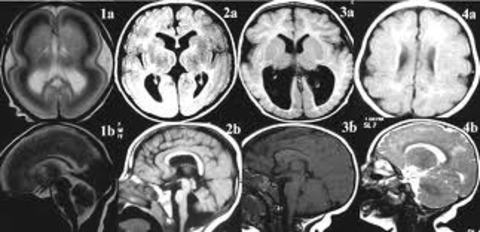

MICROCEFALIA: Es una afección en la cual la cabeza de una persona es considerablemente más pequeña de lo normal para su edad y sexo. Se presenta cuando el cerebro no logra crecer a una tasa normal, ya que el crecimiento del cráneo está determinado por el del cerebro, el cual tiene lugar en el útero y durante la lactancia. Las enfermedades que afectan el crecimiento cerebral (infecciones, trastornos genéticos y desnutrición grave) pueden ocasionar microcefalia. |

Image:

Microcephaly (image/png)